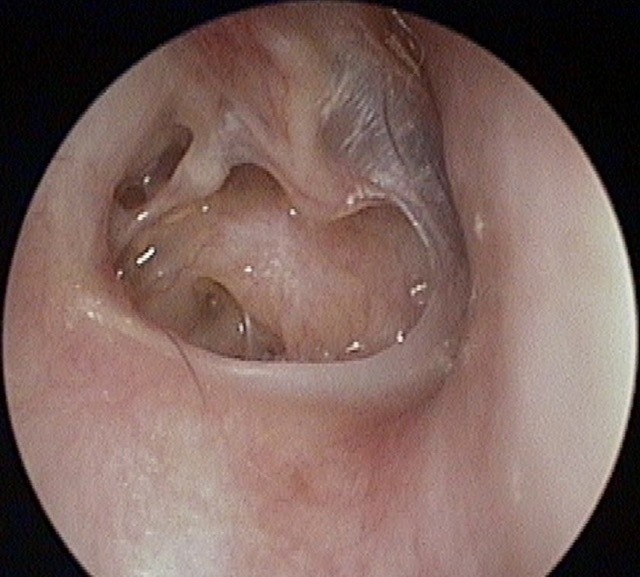

Perforation